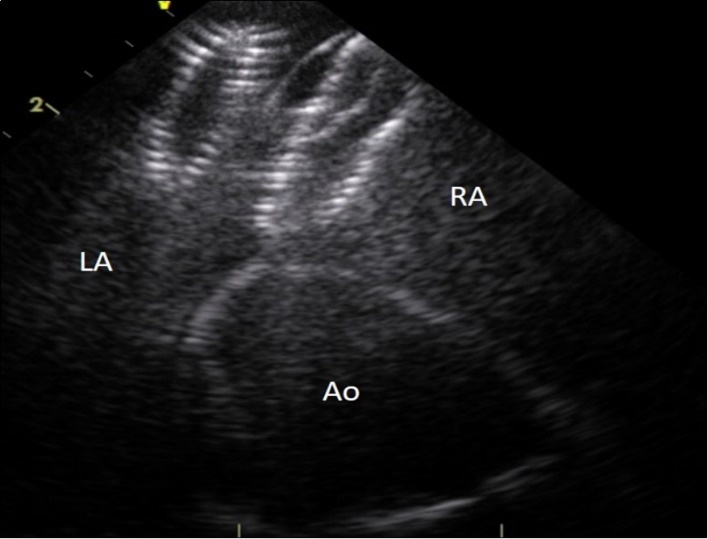

Figure 1.Entraped Amplatzer ASD closure device in the left ventricular outflow tract. LA : left atrium, AO : aorta, arrow : ASD closure device.

Figure 2.Intracardiac ultrasound picture of the ASD Amplatzer device in place on the interatrial septum. RA :right atrium. LA:left atrium. Ao :aorta